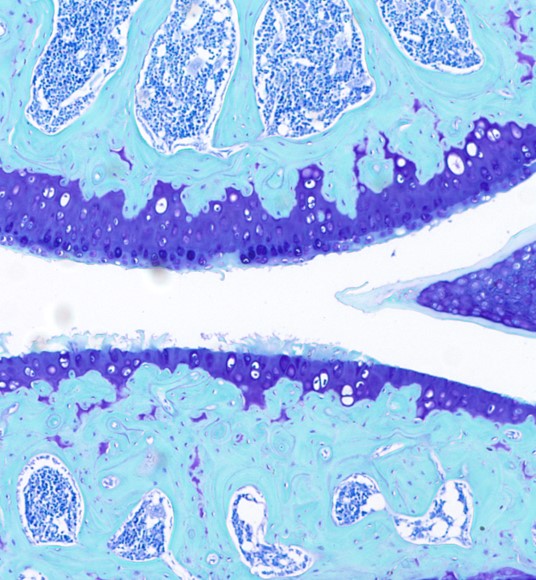

Development of chondroregenerative therapy for osteoarthritis

Activation of the parathyroid hormone receptor (Pth1r) in chondrocytes is known to inhibit cell differentiation and activate the production of the cartilage matrix. Our group discovered that in injured and degenerating cartilage, Pth1r is upregulated in chondrocytes, priming them to respond to agonist peptides. Moreover, we have established that activation of Pth1r by teriparatide (FDA-approved Forteo) is chondroregenerative in a murine model of posttraumatic osteoarthritis. Our current work is focused on mapping the signaling pathways involved with the regenerative effects of teriparatide, and we are testing its potential disease-modifying capability in early-mid-stage human osteoarthritis in an ongoing clinical trial. We are also pursuing experiments with another Pth1r agonist, abaloparatide (FDA-approved Tymlos), in murine models of osteoarthritis.